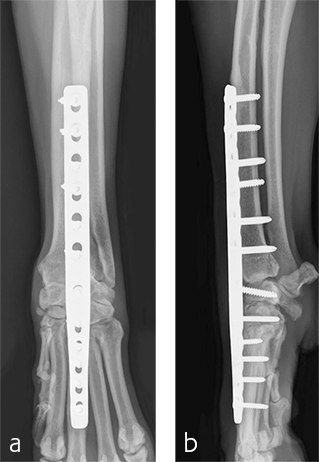

Postoperative radiographs revealed proper joint orientation and compression of the multiple antebrachiocarpal joint levels (Fig 5). Implant placement was considered excellent.

A custom fiberglass palmar splint was applied from the paw to just distal to the elbow after surgery. The splint was used for 4 weeks followed by a soft padded bandage for 4 weeks. Bandage changes were performed weekly. Activity was restricted to leash walks only for 12 weeks postoperatively. Radiographic examination 8 weeks after surgery revealed early healing of the pancarpal arthrodesis and stable implants. No complications were noted (Fig 6).